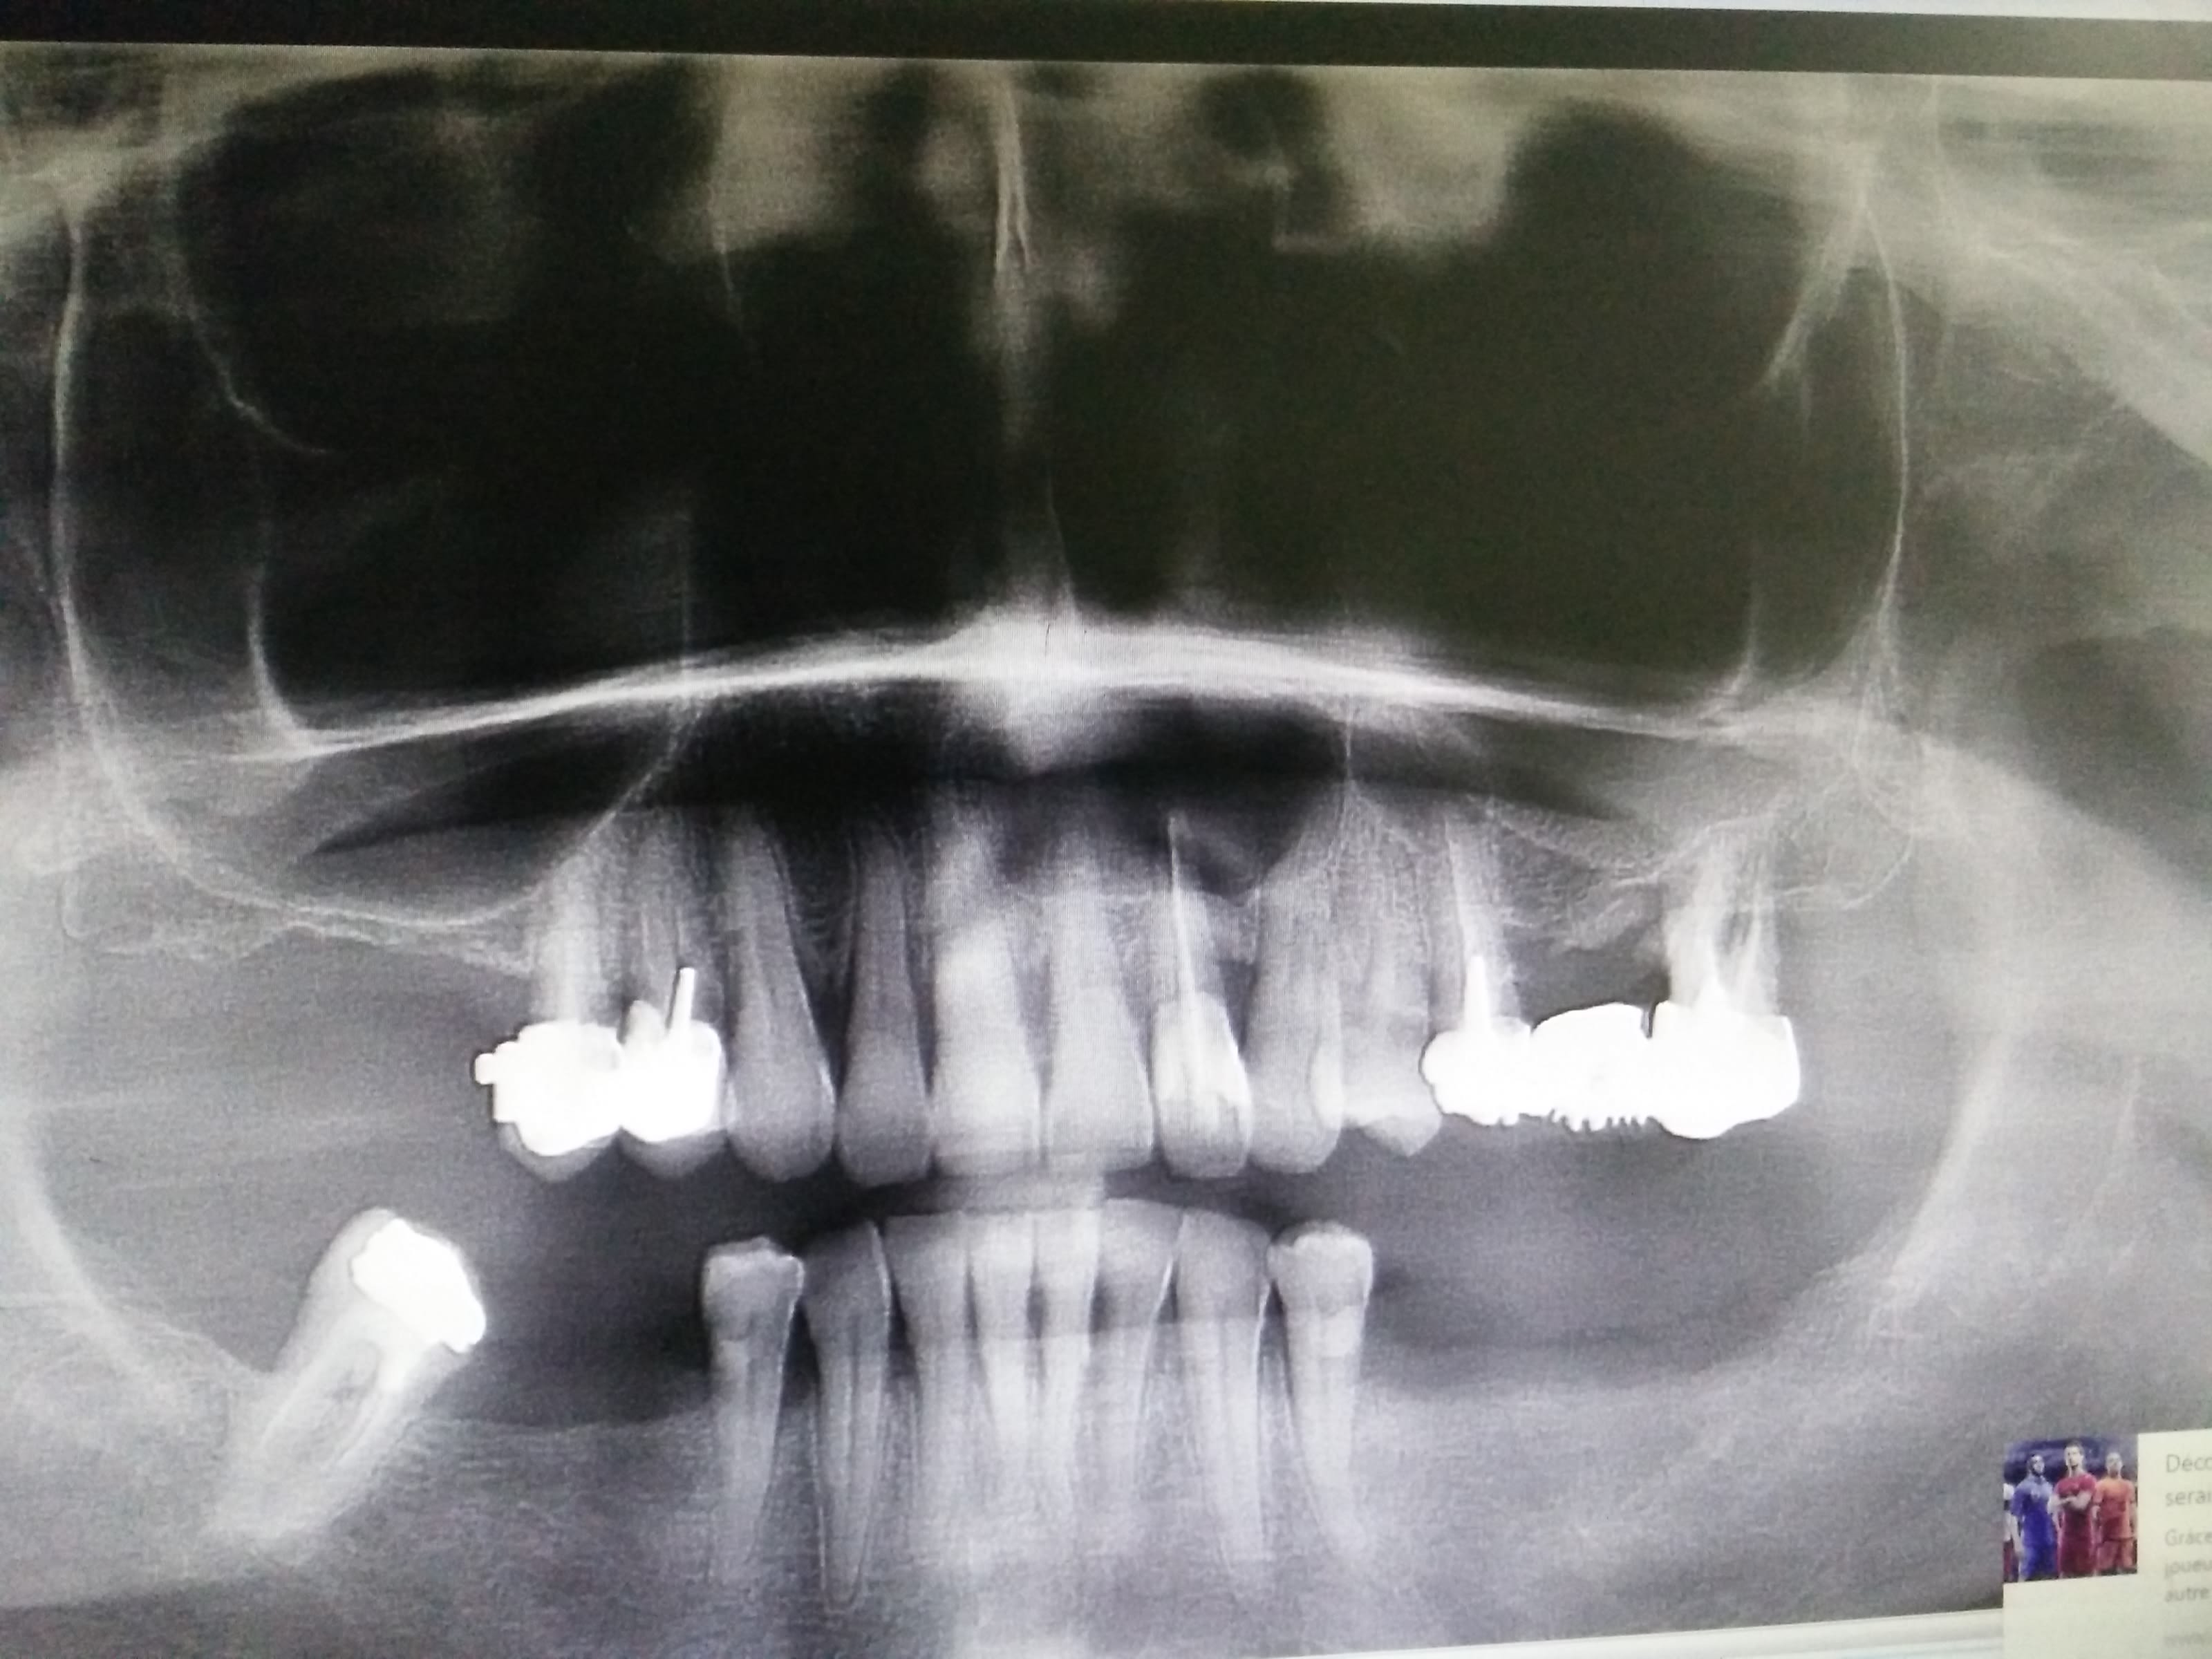

je pourrais en poster des dizaines comme ca, ca c'est un kyste d'il y a 4 semaines. Sincèrement, pas besoin du tout d'un maxillo pour ca, un dentiste suffit. Si j'ai le temps je mettrais la vidéo de ce kyste (si je la retrouve), c'est plus simple qu'un sinus lift et avec moins de risques... si tu aimes la chirurgie, que tu fais des sagesses et que tu as de quoi préparer à retro, bloque 2h de rendez vous et fais le, tu verras que c'est pas sorcier...